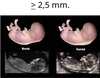

O ponto de corte definido de forma arbitrária para TN alterada é maior que 2.5 mm.

Verdadeiro: De maneira geral, uma TN maior que 2.5 mm é considerada alterada.